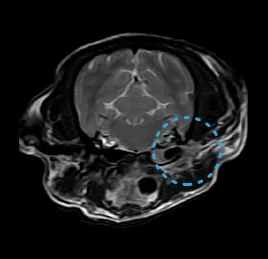

• 수막뇌염

• 허혈성 소뇌경색

• 이도 염증 - 내/중/외이염